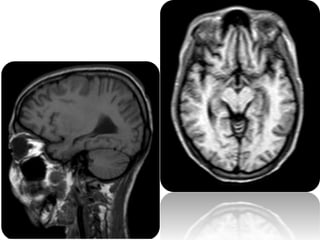

 Posterior reversible encephalopathy syndrome (PRES)

is a clinicoradiological entity

 Posterior reversible encephalopathy syndrome (PRES)

is well recognized because of its typical imaging

appearance, that is involvement of the parieto-

occipital regions

 Other brain regions may also be affected and unusual

imaging manifestations are observed frequently

B/L symmetrical parieto

occipital cortical and

subcortical regions

Frontal lobes

Cortical watershed zones

Basal ganglia

Brainstem

Cerebellum

Spinal cord